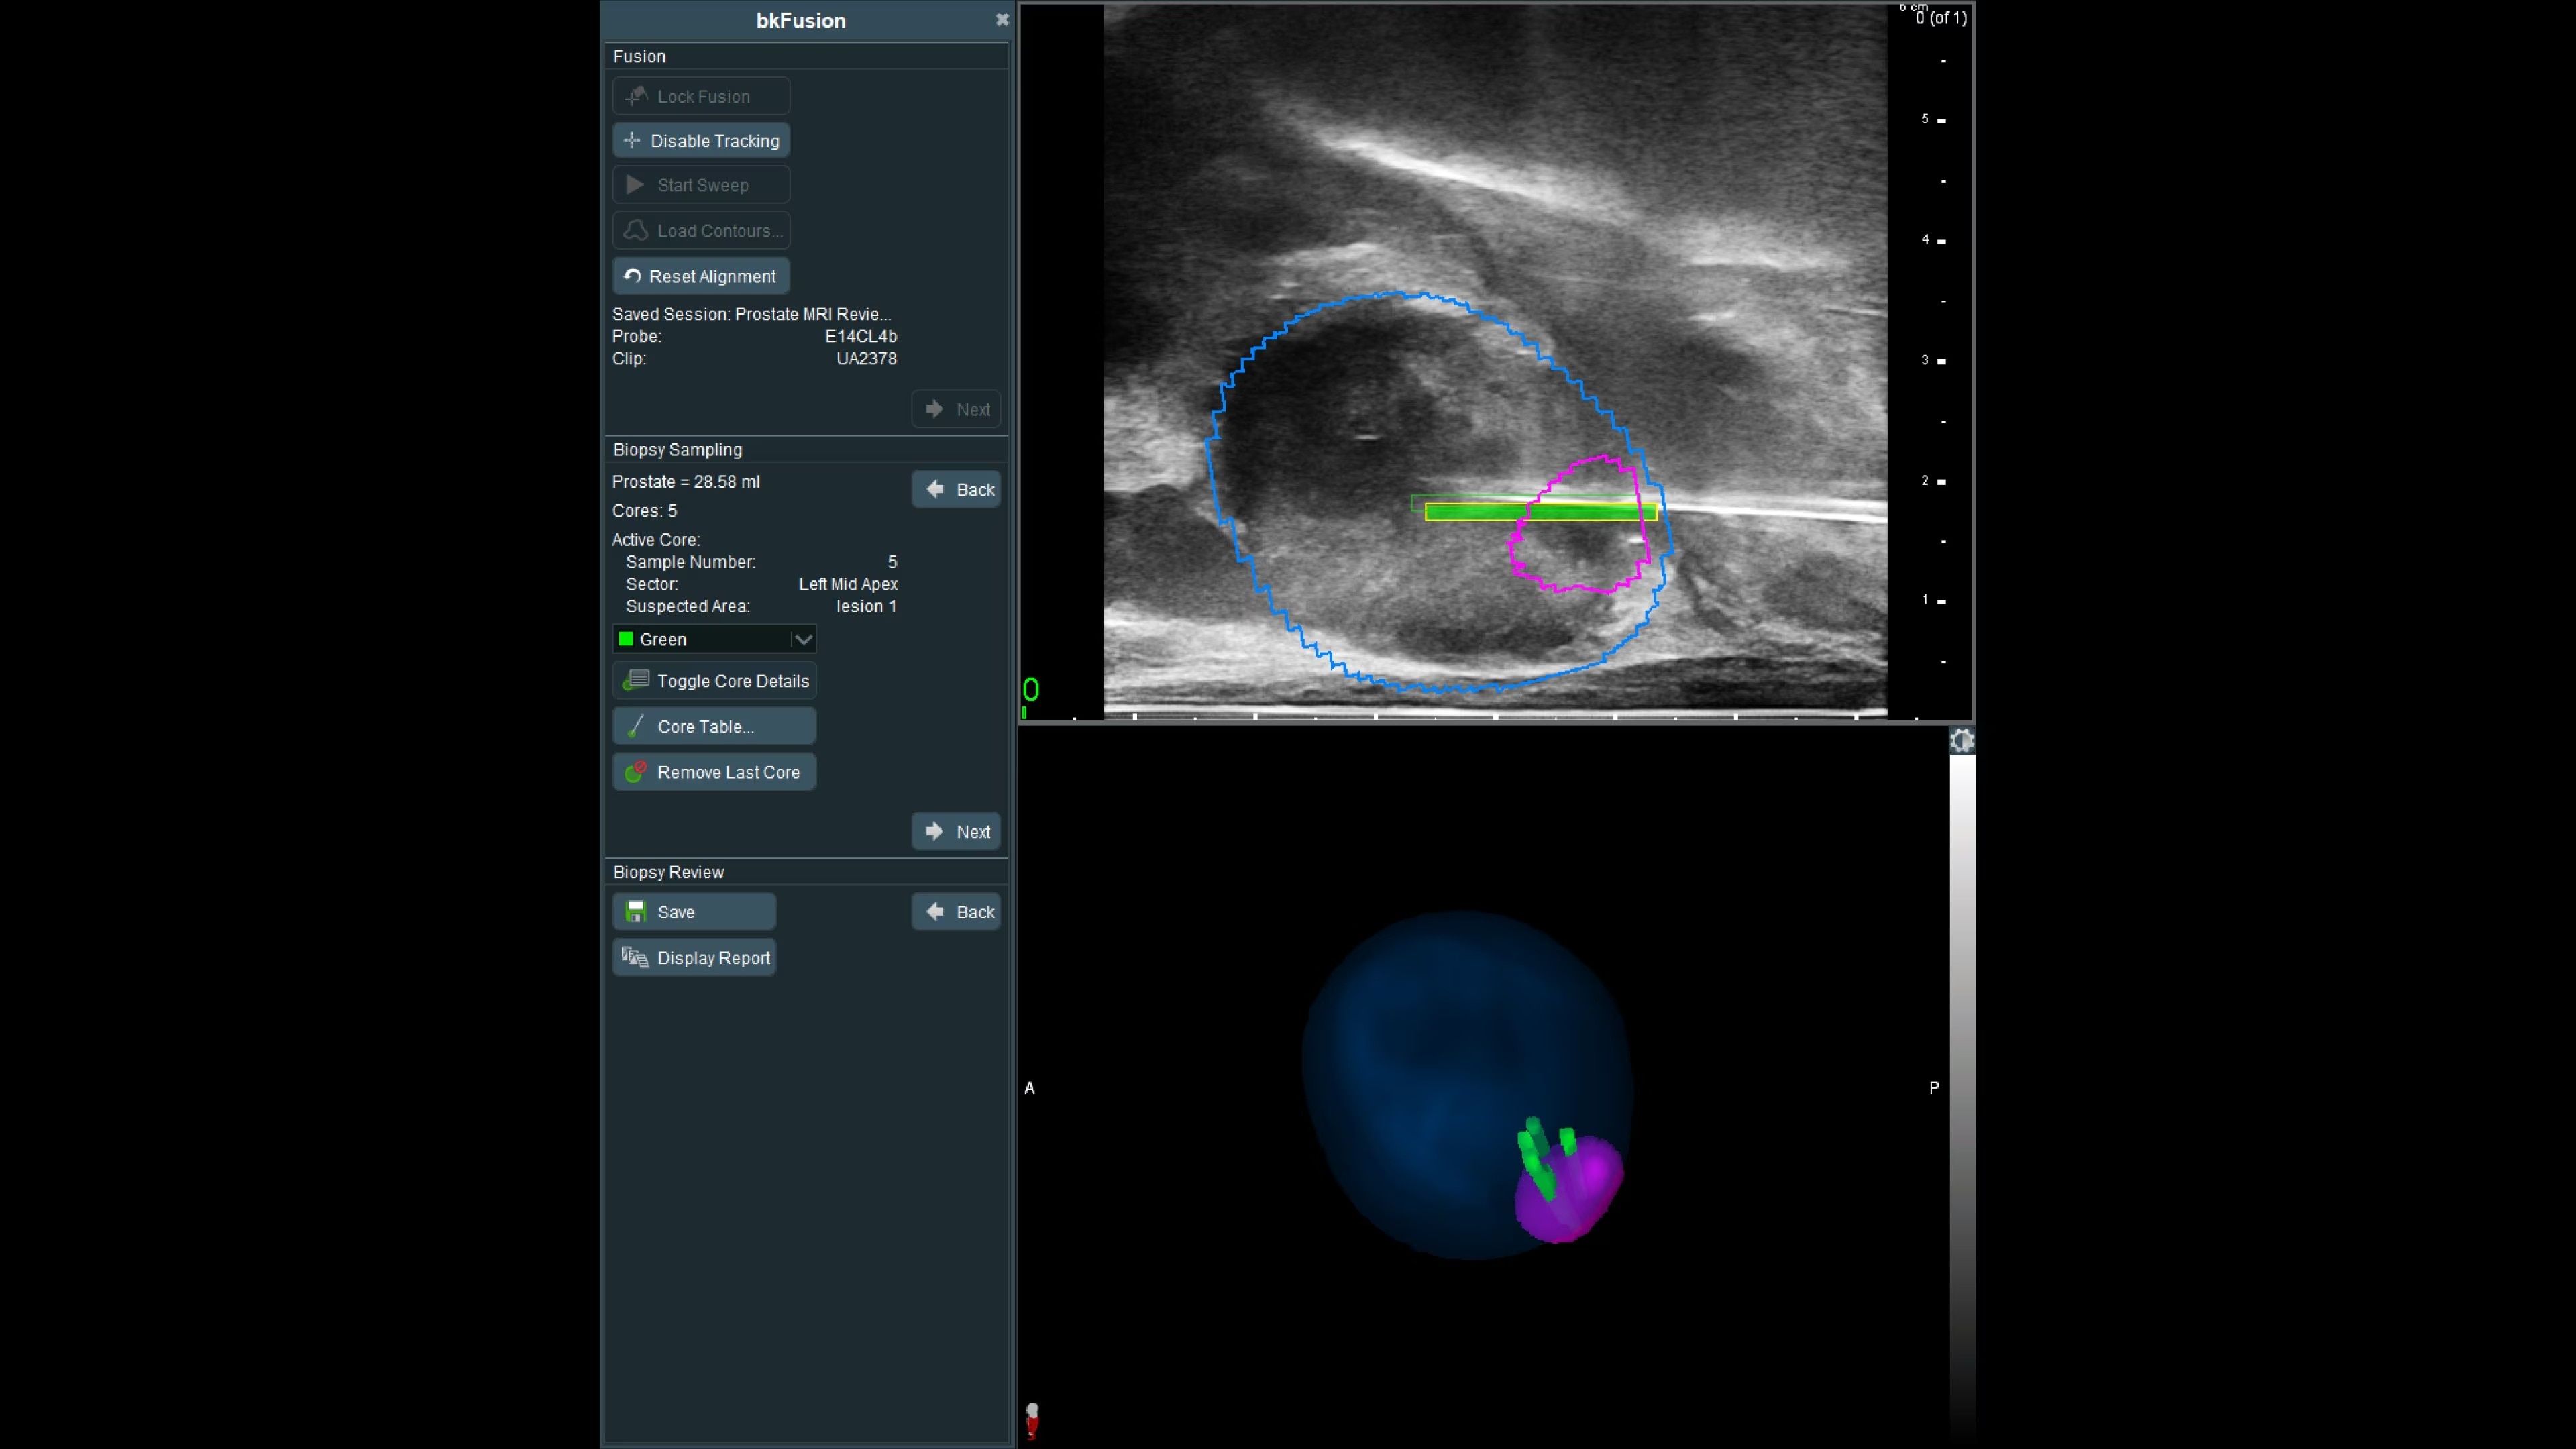

Fast, seamless operation with integrated technology

With bkFusion, complex doesn’t have to be complicated. bkFusion biopsies have been recorded to be as fast as seven minutes.² The completely integrated, single-operator solution enables seamless and efficient use by a urologist, maintaining control throughout the procedure.

Effortless imaging with no calibration or 3D sweeps

bkFusion makes prostate biopsy imaging effortless with no additional steps or disruptions to the familiar biopsy workflow. No need to calibrate the system or perform 3D sweeps. Experience this easy guided workflow in the OR or clinic. Differences in patient positioning during MRI acquisition and biopsy can result in one in six lesions being reported in a different sector than they appear during US-guided biopsy.³ bkFusion's innovative Predictive Fusion® technology optimally reorients the supine MRI into LLD or lithotomy position, preventing registration errors before the procedure begins.